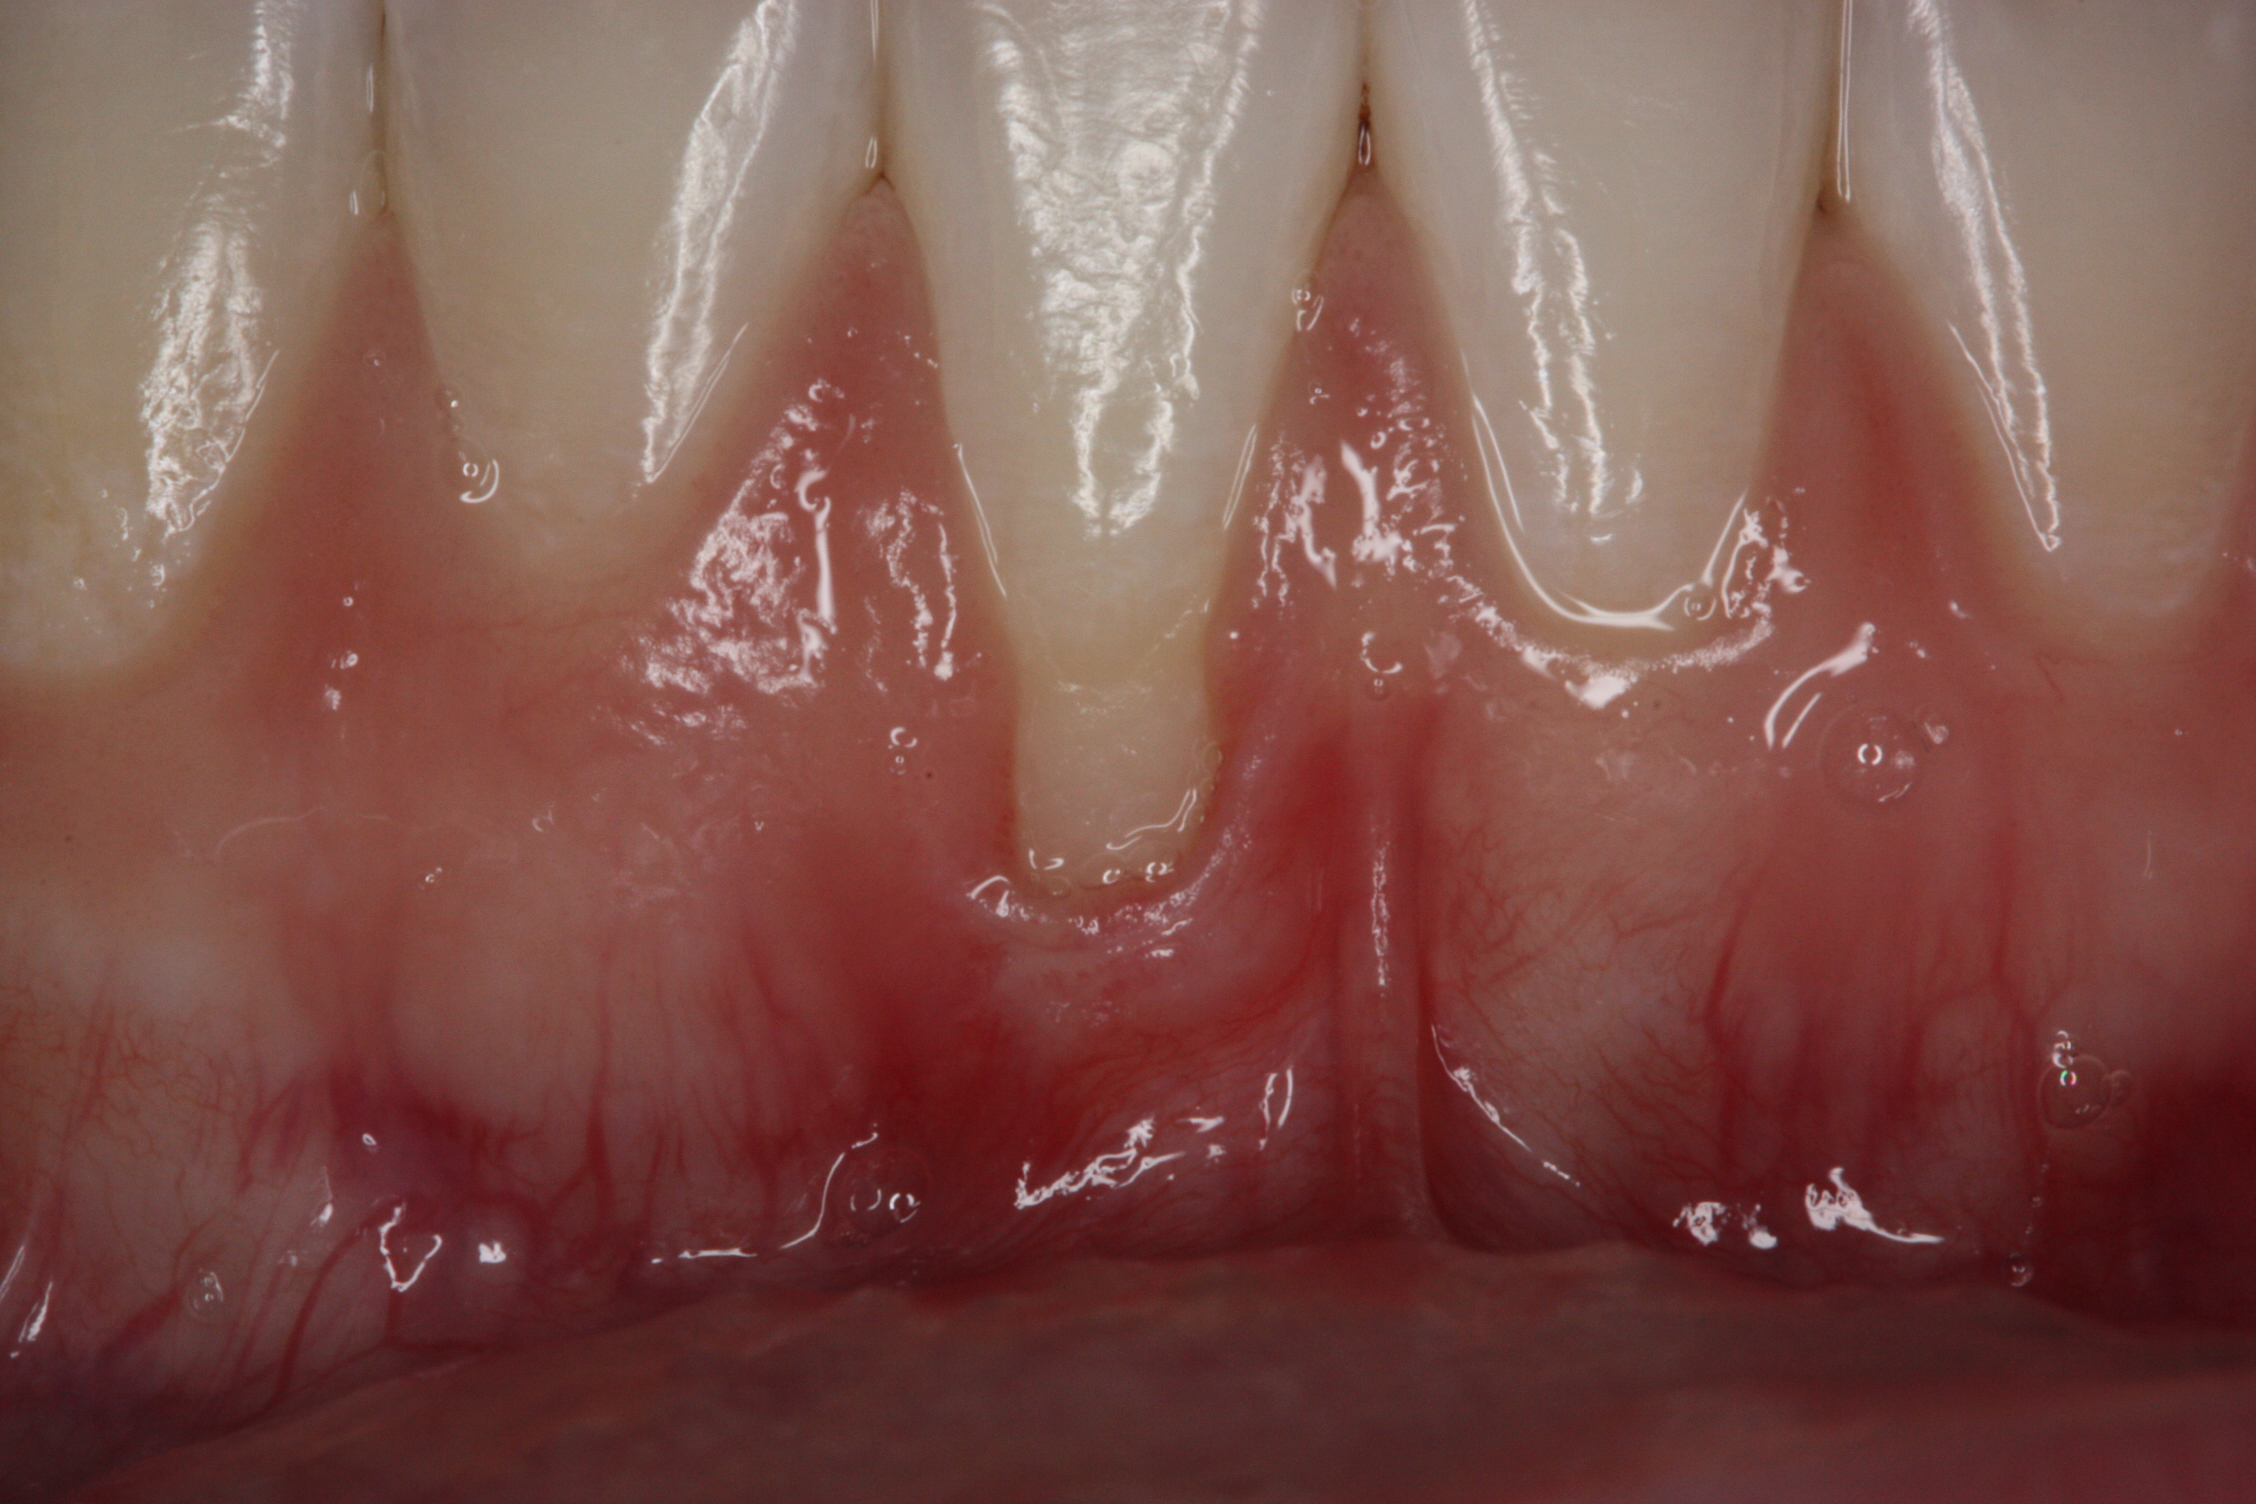

Various procedures to correct deficient gingival contours have been well documented in the dental literature.1,2 Increasing zones of attached gingiva using palatal donor tissue and the free gingival grafting procedure was introduced by Björn almost a half century ago.3 Using palatal donor tissue in the form of a free soft-tissue autograft for root-coverage procedures was reported by Miller.4 Additional procedures were reported using lateral5 or coronal repositioning6-8 of the adjacent attached gingiva via a pedicle flap or the coronal repositioning of previously grafted tissue.9,10 Miller also reported on gingival grafts placed over root surfaces to correct areas of deep-wide gingival recession.11 Further surgical advancements led to the use of subepithelial connective tissue from the palate to obtain root coverage.12-14 Figure 1 shows the pretreatment view of a mandibular central incisor, and Figure 2 depicts the post-treatment view of the site treated with a subepithelial connective tissue graft harvested from the patient’s palatal tissues.

Fig 1. Preoperative clinical view, mandibular central incisor.

Figure 1

Fig 2. Post-treatment clinical view after subepithelial connective tissue graft.

Figure 2